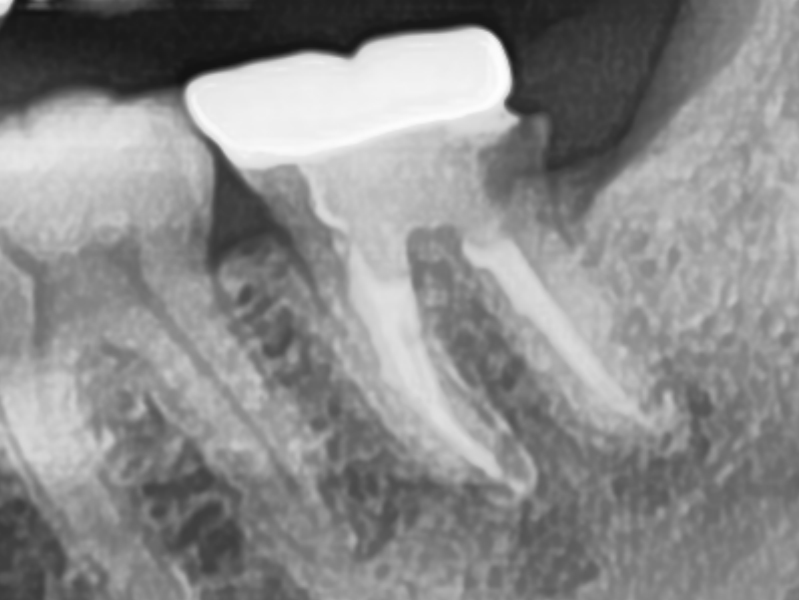

CASE.2 재신경치료

기존 신경치료 부분에 염증이 발생하여 재신경치료를 통해 치료치료전 2023.01.26 / 치료후 2023.02.27